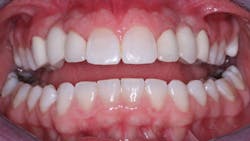

Making the decision whether to place an intracoronal restoration, an inlay, an onlay, or a crown is not a difficult one. The decision is made by considering the patient’s overall systemic and oral health characteristics, esthetic desires, and specific tooth characteristics. Currently available crowns are superb when done properly (figure 6); just don’t do them before they are indicated.